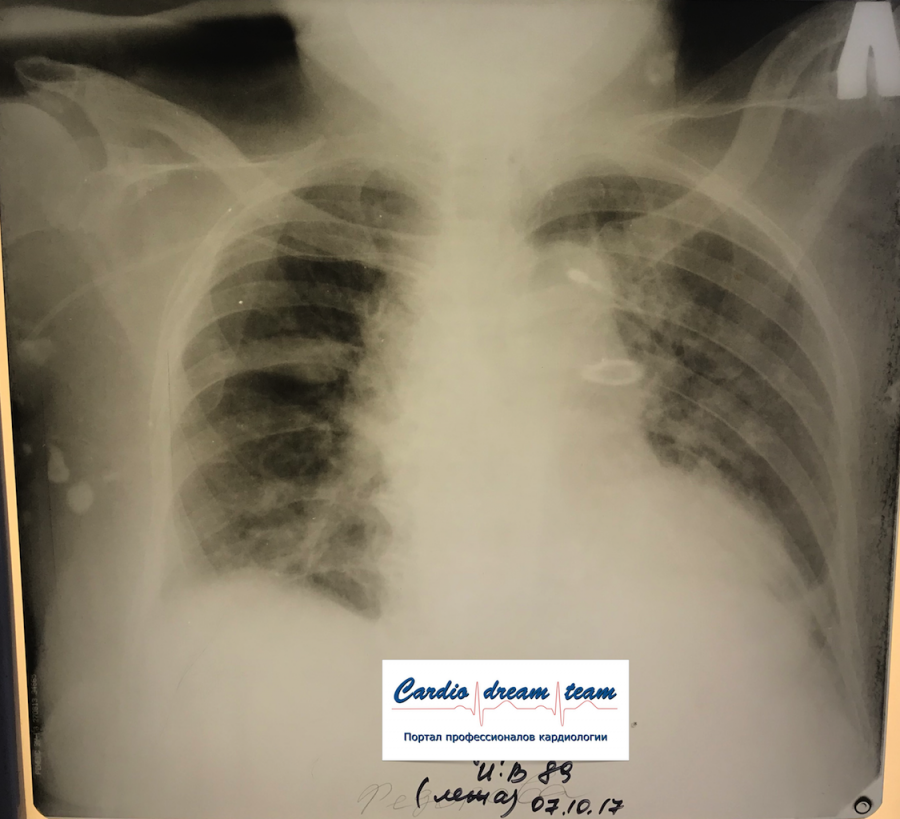

Двухсторонняя пневмония

Вложения:

IMG_0886.png

IMG_0886.png [ 759.15 KiB | Просмотров: 23128 ]

IMG_7045.png

IMG_7045.png [ 782.71 KiB | Просмотров: 23128 ]

IMG_7003.JPG

IMG_7003.JPG [ 121.75 KiB | Просмотров: 23128 ]